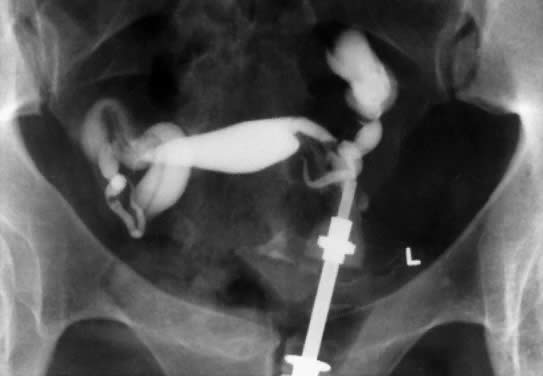

In patients with postinflammatory tubal disease, pregnancy outcome has been correlated with the presence or absence of fallopian tube rugae on hysterosalpingograms (Fig. 4). Pregnancy occurred in 61% of patients with moderate to excellent rugal patterns, whereas only 7% of patients with no demonstrable rugae conceived postoperatively.78 Laparoscopic and salpingoscopic evaluation of the endosalpinx provides another means to assess prognosis for fertility.79 However, visualization of the tubal mucosa by salpingoscopy provides even more reliable data on which to classify and score the extent of tubal disease.

Fig. 4. The hysterosalpingogram demonstrates bilateral distal ampullary fallopian tube occlusion with persistent rugal patterns or mucosal folds. Visualization of the endosalpinx by salpingoscopy provides more reliable data on which to classify and score the extent of tubal damage.